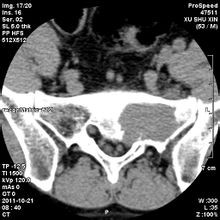

現(xiàn)年39歲的劉某,家住岱山。截止上個月,一場揮之不去的噩夢時刻纏繞著她,令她寢食難安。骶骨腫瘤,就是這么一個簡單的醫(yī)學(xué)名詞,卻給她帶來無盡的痛苦。

骶骨常見的良性腫瘤有骨母細(xì)胞瘤(成骨細(xì)胞瘤)、骨巨細(xì)胞瘤和動脈瘤樣骨囊腫等,常見的骶骨惡性腫瘤有脊索瘤、軟骨肉瘤等。手術(shù)治療是多數(shù)骶骨腫瘤的首選方案,該區(qū)域手術(shù)時出血多且不易止血,曾被視為手術(shù)禁區(qū)。